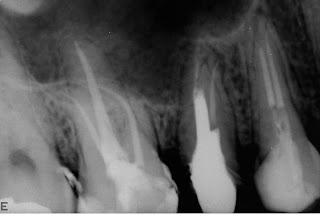

Primeiro caso com reciproc. Exploração dos canais e odontometria com limas tipo k 10 e 15 0.2.

Não foi executado pré flaring com gates, foi usada apenas a 25 0.8 reciproc com motor vdw reciproc até proximidade do crt e refinamento com limas flexofile 20 0.2 e 25 0.2.